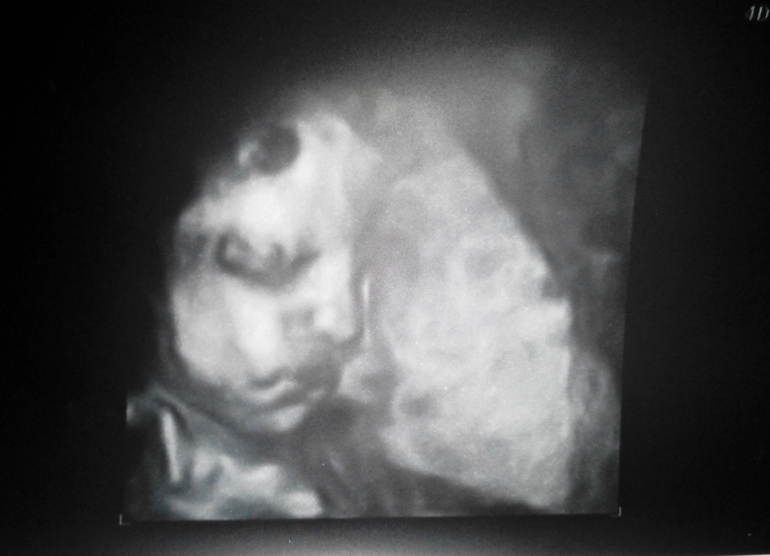

Наш мальчик уже соответствует размерам 31-32 недели, руки-ноги длинные (будет весь в папу, а не в меня-коротышку))). Вес более 1600 гр (знаю, это приблизительно), малыш долбил по датчику изо всех сил, также как стучит по моим рёбрам))). Лицом уткнулся в плаценту, как в подушку, но НС смогла нам сделать фото, пуповину накинул на шею, руку положил между ног и был очень недоволен, что мы его беспокоим. Пухленькие губки поджаты, уголки губ опущены (такое же серьёзное выражение лица было у дочки, когда я впервые её разглядела, через неделю после родов). А ещё нам подробнейшим образом показали и сфотографировали мошонку сына с яичками, прям вот во всей красе, в 3D. Хотя я не просила и не сомневалась, но папа сидел напряженный, для него это сверхважная информация))).